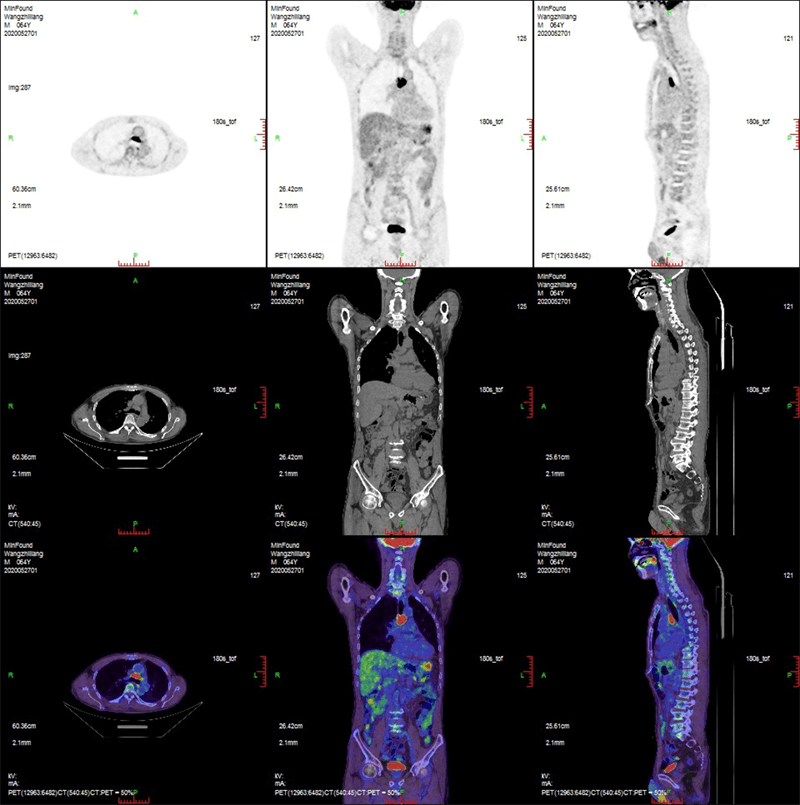

ScintCare PET/CT 720E

ScintCare PET/CT 720E uses the 4th-generation PET detector with which lutetium-yttrium oxyorthosilicate (LYSO) crystals are individually coupled to SiPM detectors without the optical conductor. This digital SiPM-based detector ensures 100% crystal coverage to the SiPM and greatly improves photons efficiency and images quality.

The 20.16 cm axial FOV compare to the conventional 16 cm axial FOV PET/CT, it speeds up the scanning process allowing greater patient throughput.

臨床畫廊